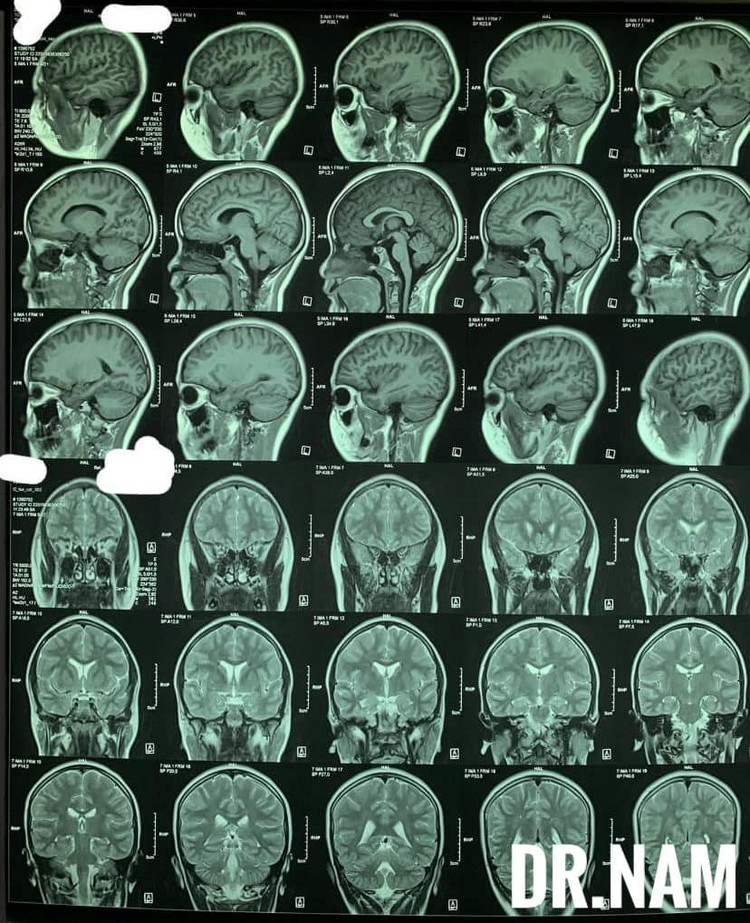

Kết quả với phim MRI sọ não tổn thương chất trắng dưới vỏ thuỳ trán đỉnh 2 bên,

Tại Bệnh viện Xanh Pon, kết quả chụp phim MRI sọ não cho thấy tổn thương chất trắng dưới vỏ thuỳ trán đỉnh 2 bên, xét nghiệm máu có tỷ lệ bạch cầu ưa axit lên đến 10%, trẻ được chọc dịch não tuỷ chẩn đoán và phát hiện dương tính với giun đũa chó mèo trong vòng 24h.